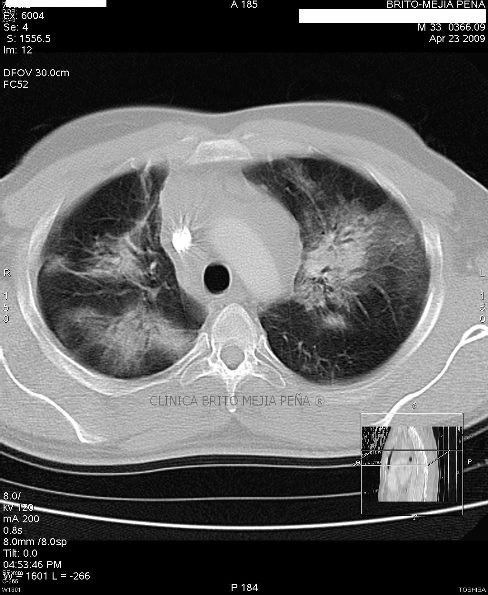

Metástasis pulmonares

Post Image